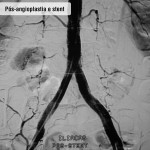

Tratamento endovascular

Pacientes com feridas necessitam de cirurgia na qual é feita punção na virilha, dilatação dos estreitamentos com balão e colocação de stent (molde metálico) para manter a artéria aberta. Com este procedimento, o paciente evita cortes, toma anestesia local e pode voltar para casa no mesmo dia (após seis horas de repouso) ou no dia seguinte. Para evitar novas lesões é imprescindível que a pessoa mude seus hábitos de vida, optando por um estilo mais saudável – inclui-se aí a prática regular de exercícios, a suspensão do fumo e o controle do colesterol e do diabetes.